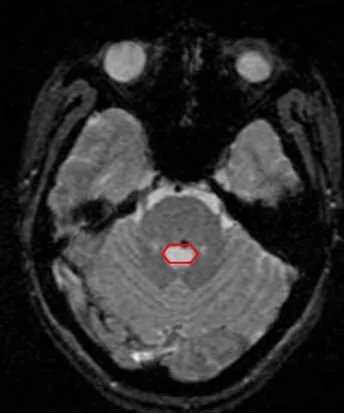

U máu thể hang: Một dị dạng mạch não

U máu thể hang là một dị dạng mạch máu ở não hoặc tủy sống, bao gồm các khoang nhỏ chứa máu. Bệnh có thể gây động kinh, rối loạn thần kinh, tăng áp lực nội sọ và xuất huyết. Chẩn đoán bằng MRI, điều trị bằng phẫu thuật hoặc xạ phẫu dao gamma. Xạ phẫu dao gamma quay là phương pháp ít xâm lấn và hiệu quả để giảm thiểu biến chứng.